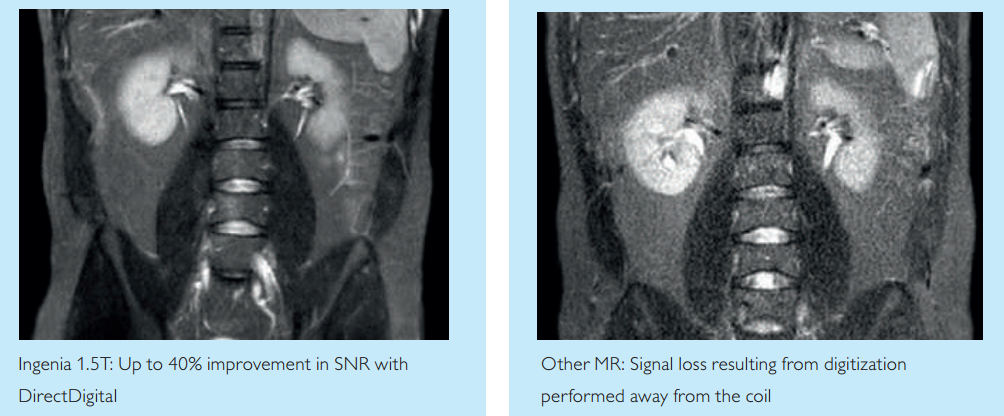

醫療設備